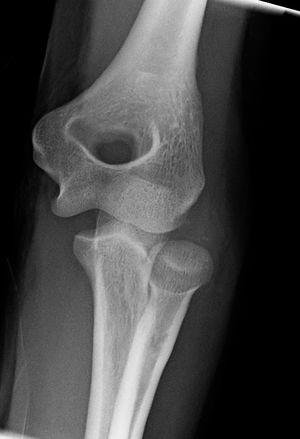

Elbow dislocation

- Elbow dislocation

- Lateral: both ulna and radius are displaced posteriorly

- AP: lateral or medial displacement with ulna/radius in their normal relationship